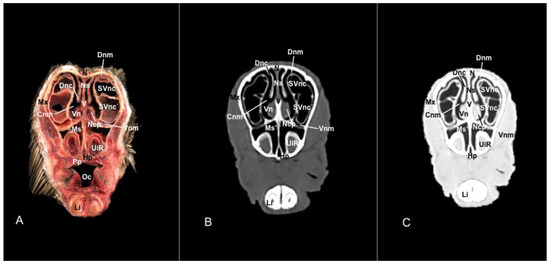

3.1. Anatomical Sections

3.2. Computed Tomography (CT)